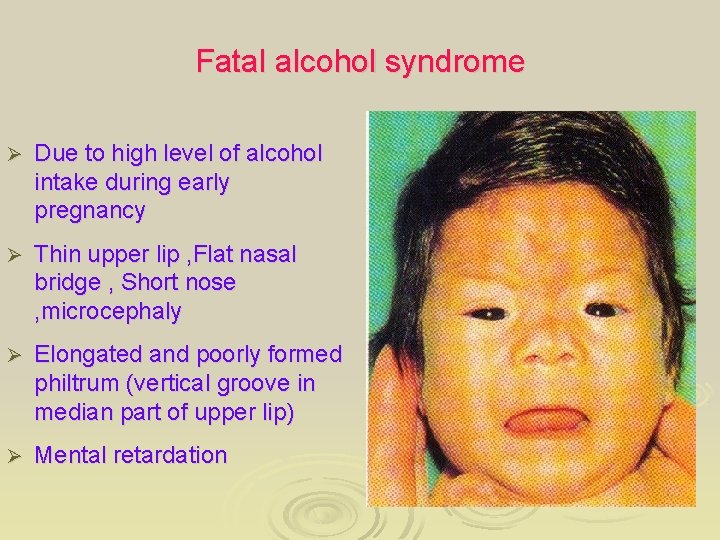

Fatal alcohol syndrome Ø Due to high level of alcohol intake during early pregnancy Ø Thin upper lip , Flat nasal bridge , Short nose , microcephaly Ø Elongated and poorly formed philtrum (vertical groove in median part of upper lip) Ø Mental retardation